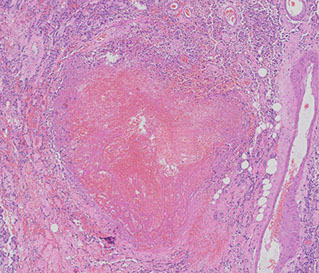

Temporal (Giant cell) aortitis/arteritis

MC vasculitis in large (and medium-sized) arteries

- usually affects branches of the carotid artery (ie temporal a.) in elderly females

Micro: Fragmented elastic fibers, giant cell / granulomatous (macros and lymphos) response and intimal thickening which reduces lumen

- giant cells not required for temporal arteritis (in ~75%), only destruction of internal elastica with inflammation

-false negatives due to focal distribution and steroid tx before biopsy (3-5 cm); polymyalgia rheumatica (muscle pain)

Dx: Temporal a. bx

Tx: high-dose steroids (do not wait for bx results to tx - Emergency!!)

Giant cell arteritis of the breast. The vessel wall has been replaced by granulomatous inflammation. The process has compressed the vessel lumen to near-complete obstruction. A giant cell is shown in this field. B, Giant cell arteritis of the breast. Granulomatous inflammation and fibrinoid necrosis are shown within the wall of this vessel. C, Giant cell arteritis of the breast. The special elastin stain highlights the fragmentation of the internal elastic

lamina in this vessel (hematoxylin-eosin, original magnifications320 [A and B]; original magnification320 [C]).